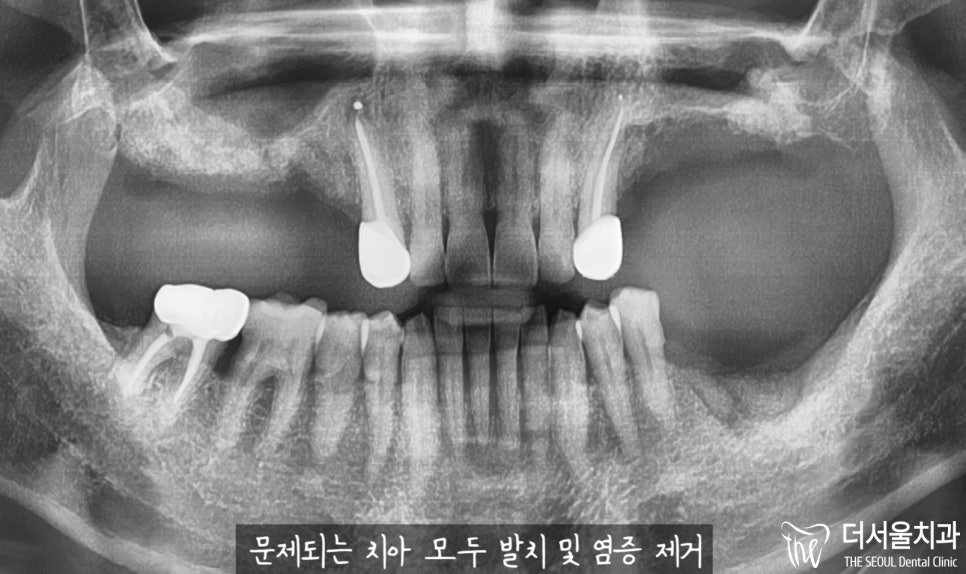

반갑습니다. 잠실 더서울 치과 입니다. 오늘 소개해 드릴 사례는 예전에 찾아오셔서 좌측 아래 어금니 임플란트 식립을 받으셨던 환자분께서 우측